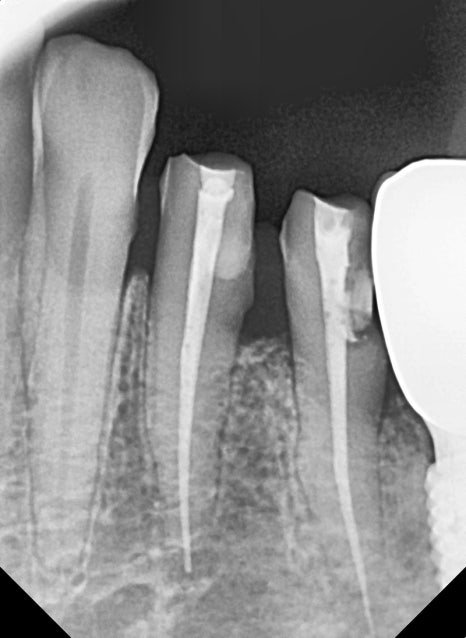

엑스레이 사진을 통해

임플란트에 문제가 없는지 확인하려는 찰나,

230926 치아 사이 충치

임플란트와 바로 옆 자연치아 틈새에 약간의 충치가

진행되고 있는 걸 발견했습니다.

충치가 심하지 않아

지금 바로 치료하기에는 아까워서,

환자분께 치간칫솔로 관리 잘해주시고

다음 번 정기검진일에 꼭 내원해달라고 말씀드렸던 기억이 납니다.

1년 반 전 엑스레이 사진과 그 후 사진입니다.

충치 크기 차이가 꽤 많이 나죠?